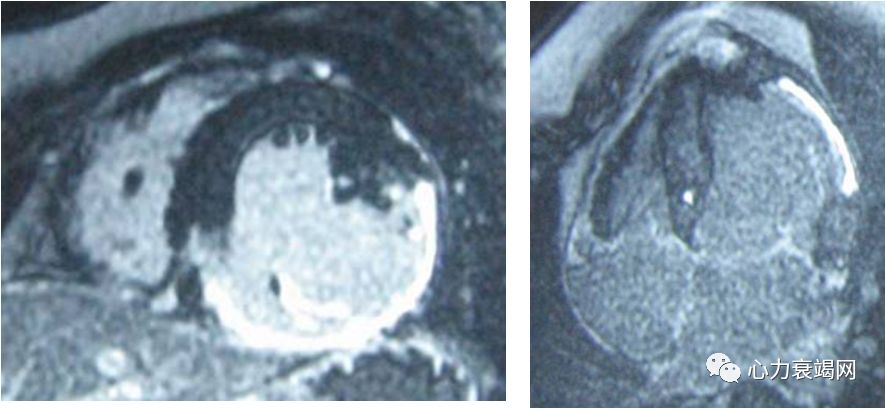

外院ECHO:扩张型心肌病,左房、左室扩大,左室舒张、收缩功能降低,二尖瓣少量返流,EF27- 45%。

节段性运动异常

延迟扫描见左室多发异常强化,考虑心肌缺血坏死改变